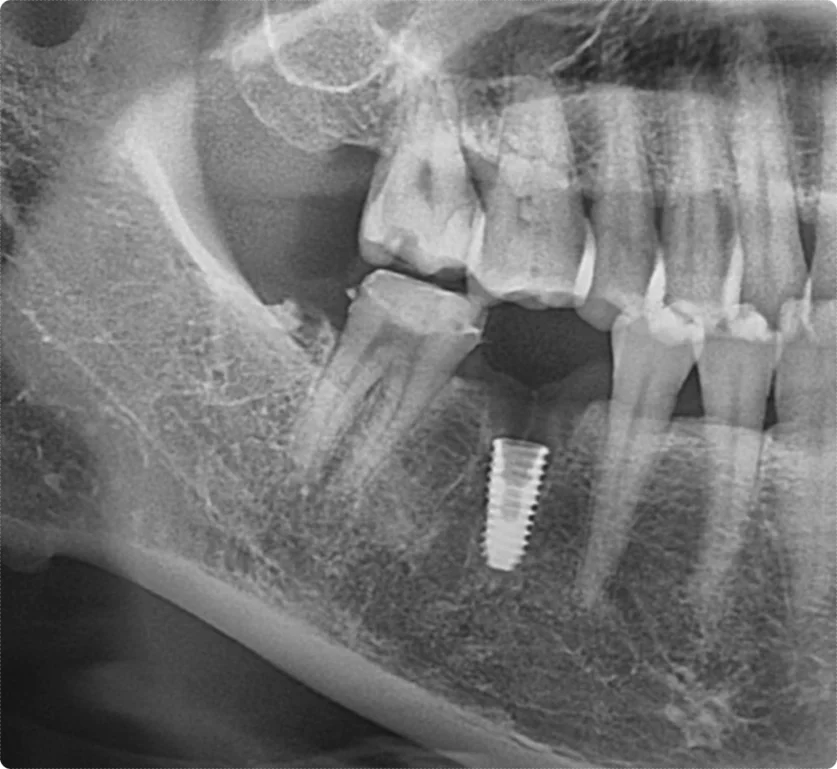

두 번째 환자분은 같은 날 내원하셨지만, 치아 손상이 훨씬 심했습니다.

치아에 명확한 파절과 균열이 있었고, 환자분 스스로도 심한 통증을 느껴 내원하셨습니다.

손상이 너무 심하여 자연치 보존이 어렵다고 판단했고, 발치 후 임플란트를 진행하게 되었습니다.